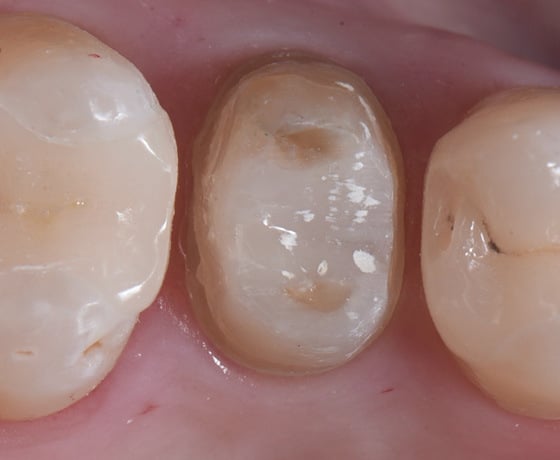

Pretrattamento sabbiatura con 30 µm di Al2O3, pulizia con etanolo e cemento composito 3M™ RelyX™ Universal.

Risultato dopo la cementazione.